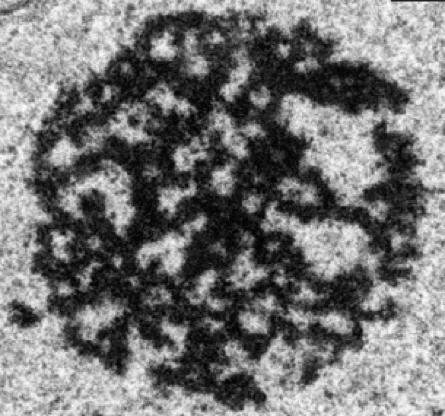

MIAMI, October 6, 2016 -- A study published today by researchers at Sylvester Comprehensive Cancer Center at the University of Miami Miller School of Medicine describes that certain proteins playing a role in cancer progression and metastasis are stored as amyloid bodies in dormant cancer cells. Once the amyloid bodies disaggregate, the cancer cells become active again. The findings were published in the journal Developmental Cell today.

Amyloid bodies are known to play a role in the development of neurological diseases such as Alzheimer's and Parkinson's disease but their contributions to the progression of cancer have been largely unknown. This discovery points to a new avenue for the treatment of various types of cancers by applying knowledge we have gained from neuroscience to tumor biology.

"The amyloid state of protein organization is typically associated with debilitating human neuropathies and rarely observed in physiology," said Stephen Lee, Ph.D., director of the Tumor Biology Program at Sylvester, professor of biochemistry and molecular biology at the Miller School, and corresponding author of the study. "Yet, we found that a large number of proteins are stored as amyloid bodies in cancer cells that are dormant. The heat shock chaperone pathway can disaggregate the amyloid bodies and turn the dormant cancer cells into active, progressing cancer cells."